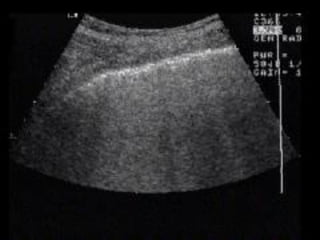

The FAST view…

 Probe goes longitudinally in right mid axillary line with

marker towards head.

 Look for IVC running longitudinally adjacent to the liver

crossing the diaphragm

 Track superiorly until it enters the RA confirms it’s the IVC not

the aorta

The FAST view… Probe goes longitudinally in right mid axillary line with marker towards head.  Look for IVC running longitudinally adjacent to the liver crossing the diaphragm  Track superiorly until it enters the RA confirms it’s the IVC not the aorta